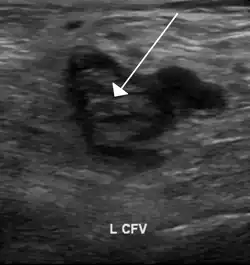

Trombo na veia femoral visto em uma ecografia

A trombose venosa profunda pode ser suspeitada através de achados do exame físico. Um sinal sugestivo da doença é o Sinal de Homan. Os exames confirmatórios de TVP incluem o ecodoppler venoso dos membros inferiores, análise do dímero D e angiografia.[10]